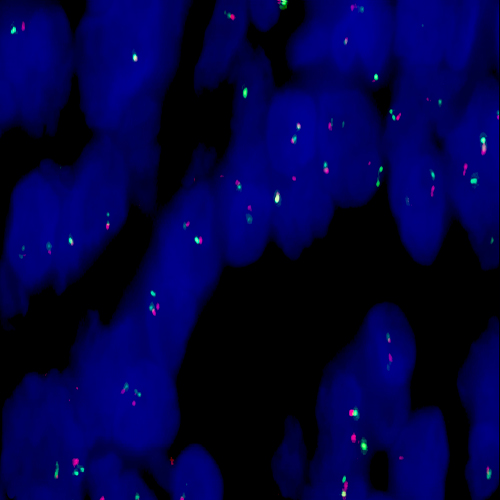

Langerin is a type II transmembrane C-type lectin which has mannose-binding specificity. It is a 40 kD protein restricted to Langerhans cells that is involved in the internalization of cell surface material in these immature dendritic cells. Dendritic cells are antigen-presenting cells that are required for initiation of a specific T-cell-driven immune response. These cells are found in non-lymphoid tissue as immature cells whose primary function is to capture antigens through specialized surface membrane endocytic structures or through macropinocytosis. The dendritic cells migrate to secondary lymphoid tissue and mature into efficient antigen presenting cells. A part of the maturation process includes the loss of adhesion receptors such as E-cadherin and the disappearance of Birbeck granules. Although Langerin is reported to be located on the cell surface, it can be rapidly internalized following ligand capture into Birbeck granules. In fact, Langerin is a potent inducer of membrane superimposition and zippering leading to Birbeck granule formation. In reports it has been suggested that the induction of Birbeck granules is a consequence of the antigen-capture function of Langerin allowing passage into these organelles and providing access to a non-classical antigen processing pathway.